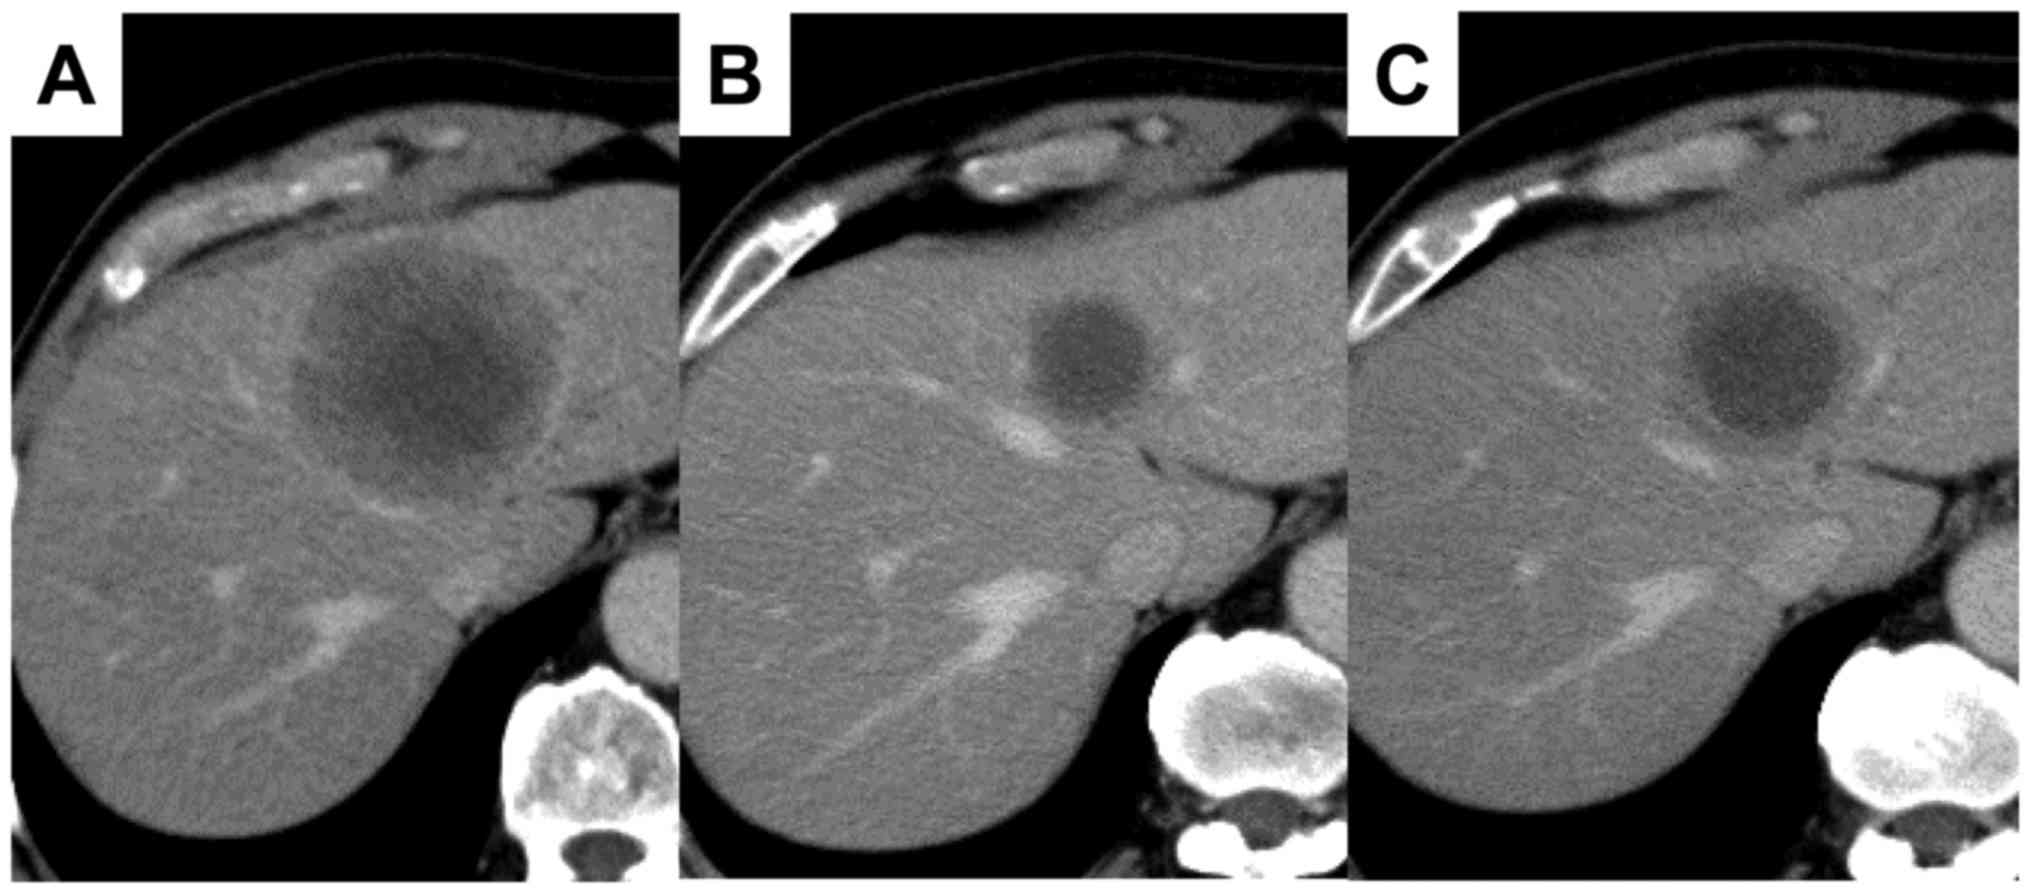

Serum ProGRP and NSE levels predicting small cell lung cancer transformation in a patient with ALK rearrangement‑positive non‑small cell lung cancer: A case report

The resistance mechanisms to anaplastic lymphoma kinase (ALK) inhibitors comprise ALK gene variations, such as ALK point mutations and copy‑number gains, the activation of bypass signaling through the activation of other oncogenes and small cell lung cancer (SCLC) transformation. To date, few studies have investigated whether tumor markers for SCLC correlate with the SCLC transformation in EGFR‑mutant NSCLC and ALK‑positive non‑SCLC (NSCLC). The present case study reported a patient with SCLC transformation after alectinib treatment. The patient exhibited elevation of pro‑gastrin‑releasing peptide precursor and neuron‑specific enolase levels, which may be predictive of SCLC transformation during the resistance to ALK‑tyrosine kinase inhibitors.

Figure 1

Figure 2

Figure 3